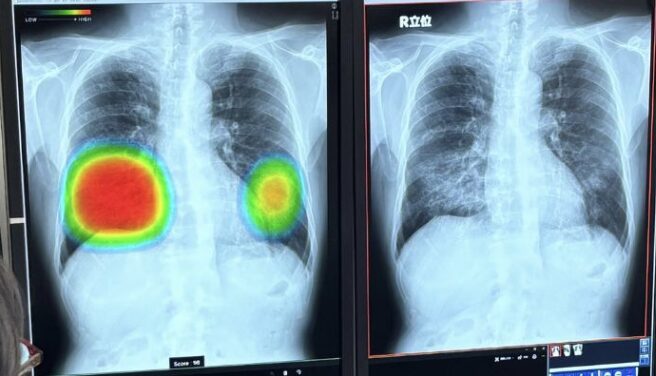

この写真はイメージ図で私の画像ではありませんが、AIによる解析で“怪しい部位”が黄緑色にマーキングされており、まるで自分の体の中を見透かされたような感覚になります。

最新のAI技術が医療現場で活躍する時代。

歯科医療の分野でも、こうしたAIによる診断サポートが当たり前になる日がもうすぐやって来るだろうと感じました。